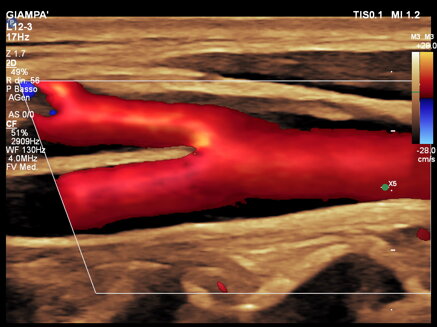

L’ecocolordoppler dei tronchi sovraortici (TSA) è un esame che permette di studiare la morfologia dei vasi, riconoscere le lesioni aterosclerotiche (placche) e la loro gravità. L’ecocolordoppler fornisce immagini a colori (rosso e blu) dei flussi venosi e arteriosi evidenziando anche le più piccole lesioni delle pareti dei vasi consentendo di valutarne con precisione l’entità. L’ecocolordoppler dei tronchi sovraortici viene richiesto per l’inquadramento di un paziente a seguito di un attacco ischemico cerebrale per la diagnosi di aneurisma e per lo studio della arterie in pazienti con fattori di rischio cardiovascolare quali ipertensione arteriosa, ipercolesterolemia, fumo, ecc.